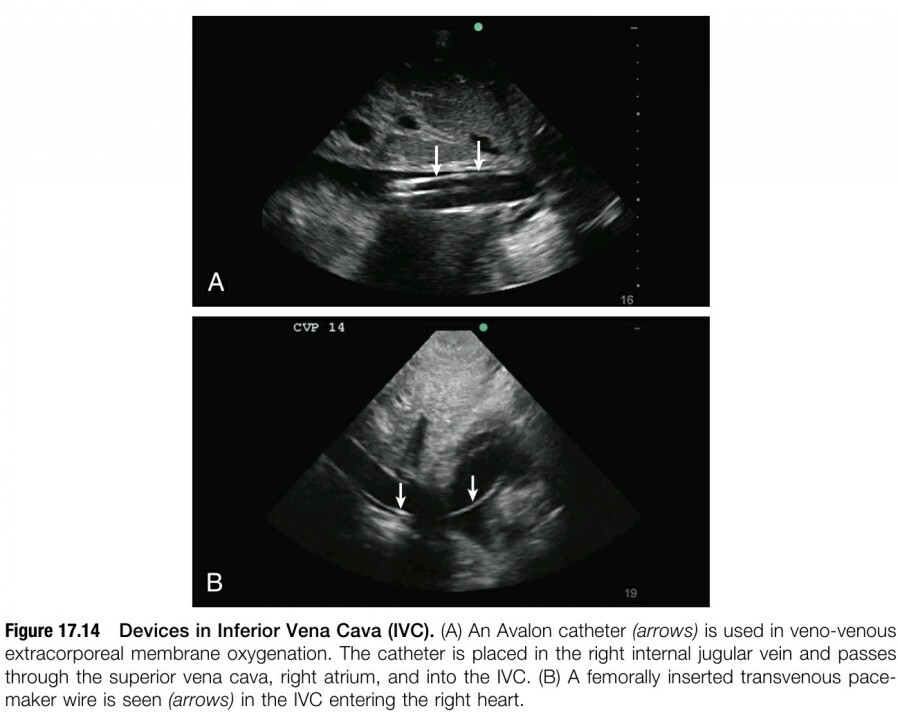

4. DEVICE PLACEMENT

증환자에서 여러 device들이 IVC를 통해 삽입된다(eg, femorally inserted temporary pacemakers, bicaval veno-venous catheters for extracorporeal membrane oxygenation [ECMO], IVC filters, etc.). IVC ultrasound를 이용해서 precedure 동안에 placement가 잘 이루어졌는지, inadvertent dislodgement나 procedure 후 migration이 일어나지 않았는지 확인할 수 있다(figure 17.14).